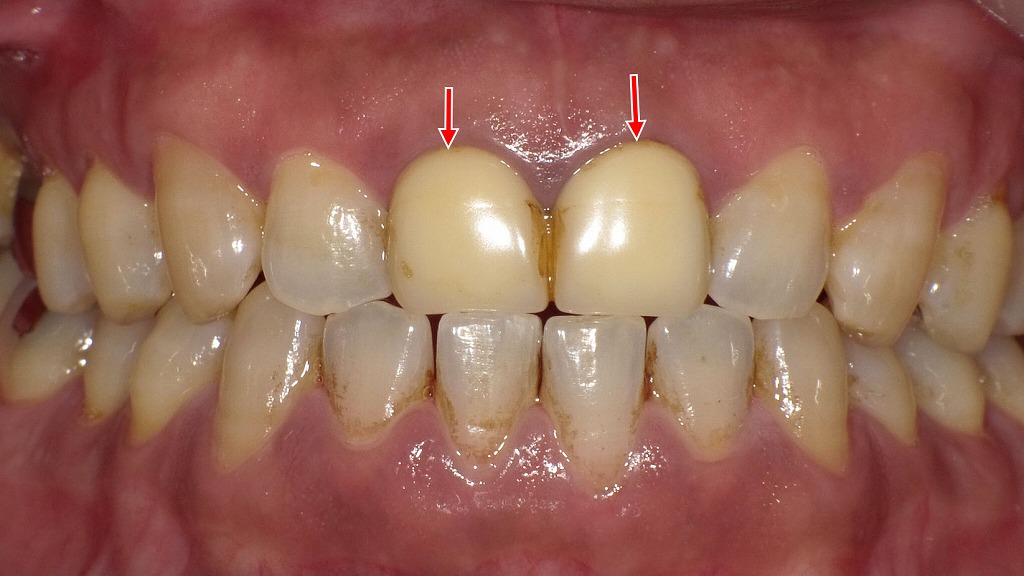

📸硬質レジン前装冠正面観

右上顎2番から左3番と右下顎3番から1番までに硬質レジン前装冠が装着されています。(矢印の歯)

着色が顕著で破折部も見られます。

硬質レジン前装冠は白い見た目で、前歯の審美性をある程度再現できますが、時間が経つと変色や摩耗が目立つことも。

写真は硬質レジン前装冠が4歯に装着されています。(矢印)

プラスチック素材である硬質レジン部分は、吸水性があるため色素を取り込んで時間の経過とともに変色しやすいという特徴があります。 特に、コーヒーや紅茶、喫煙などの習慣がある方は、変色が顕著です。